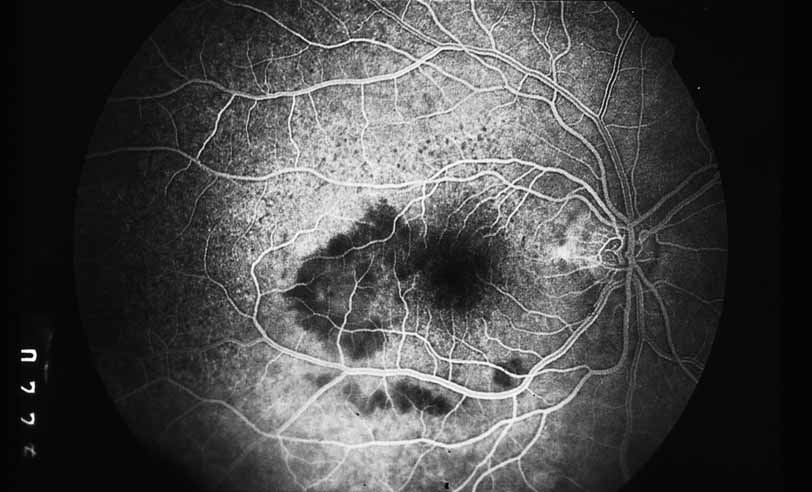

Fig. 1 Serpiginous choroiditis. Early frame of the fluorescein angiogram shows hypofluorescent and hyperflourescent patches extending outward from the optic nerve in a serpiginous pattern (Courtesy of Joseph Michaelson).

Fig. 2 Serpiginous choroiditis. Late frame of the fluorescein angiogram shows extensive staining of previously hypofluorescent zones, with continued hypofluorescence, characteristic of the acute phases of serpiginous choroiditis (Courtesy of Joseph Michaelson).